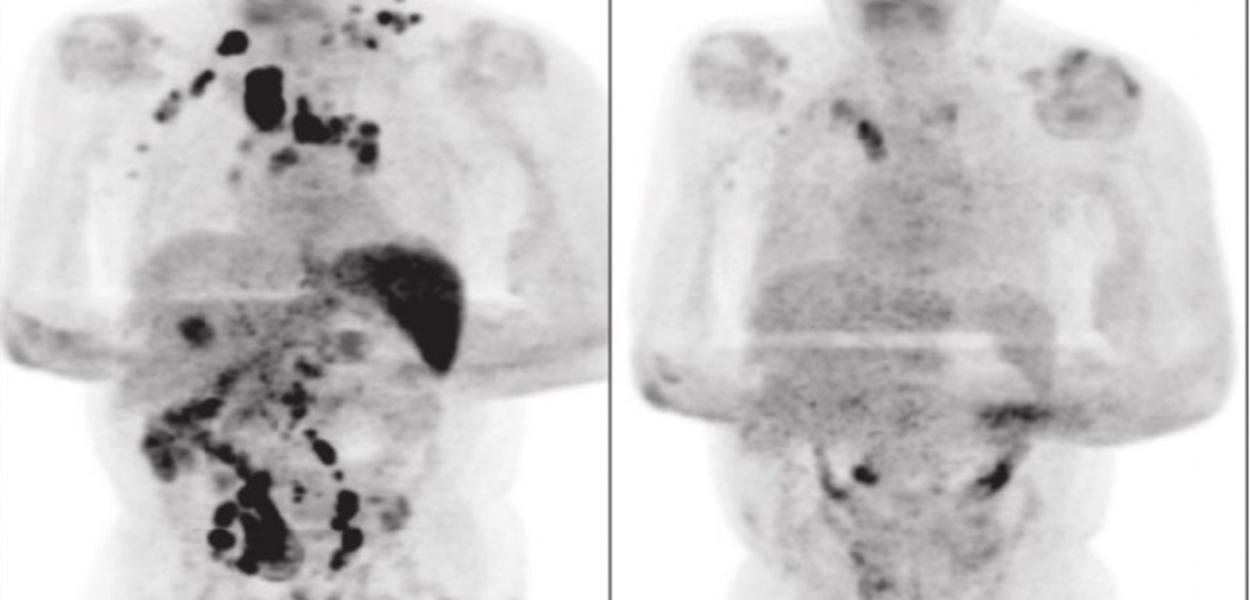

Remissão da doença antes e após diagnóstico de coronavírus (Foto: Reprodução/British Journal of Haematology)

247 - Um homem de 61 anos diagnosticado com linfoma de Hodgkin, tipo de câncer que se origina no sistema linfático, teve uma remissão da doença após contrair o coronavírus. O linfoma está sob controle, mas o paciente não é considerado curado. O caso foi publicado no periódico British Journal of Haematology no dia 2 de janeiro deste ano. A informação foi publicada pela coluna Viva Bem, no portal Uol.

Depois de quatro meses, a equipe médica fez um exame de tomografia, depois de quatro meses. Foi constatada a diminuição do inchaço dos nódulos (sintomas do linfoma) e a remissão generalizada.